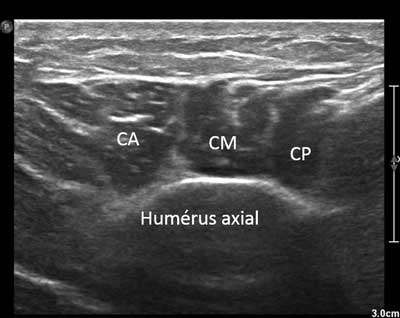

Figure 17

Axial view of the distal and lateral part of the deltoid muscle. CA: Anterior chief, CM: Medium chief, CP: Posterior chief.